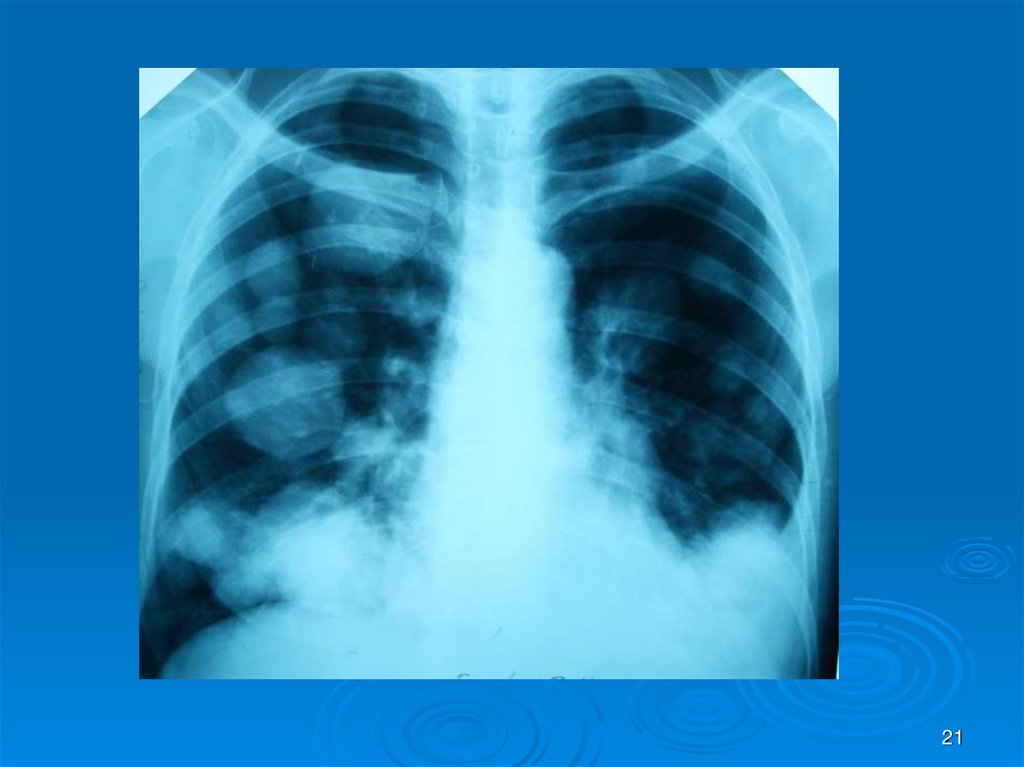

21.

21